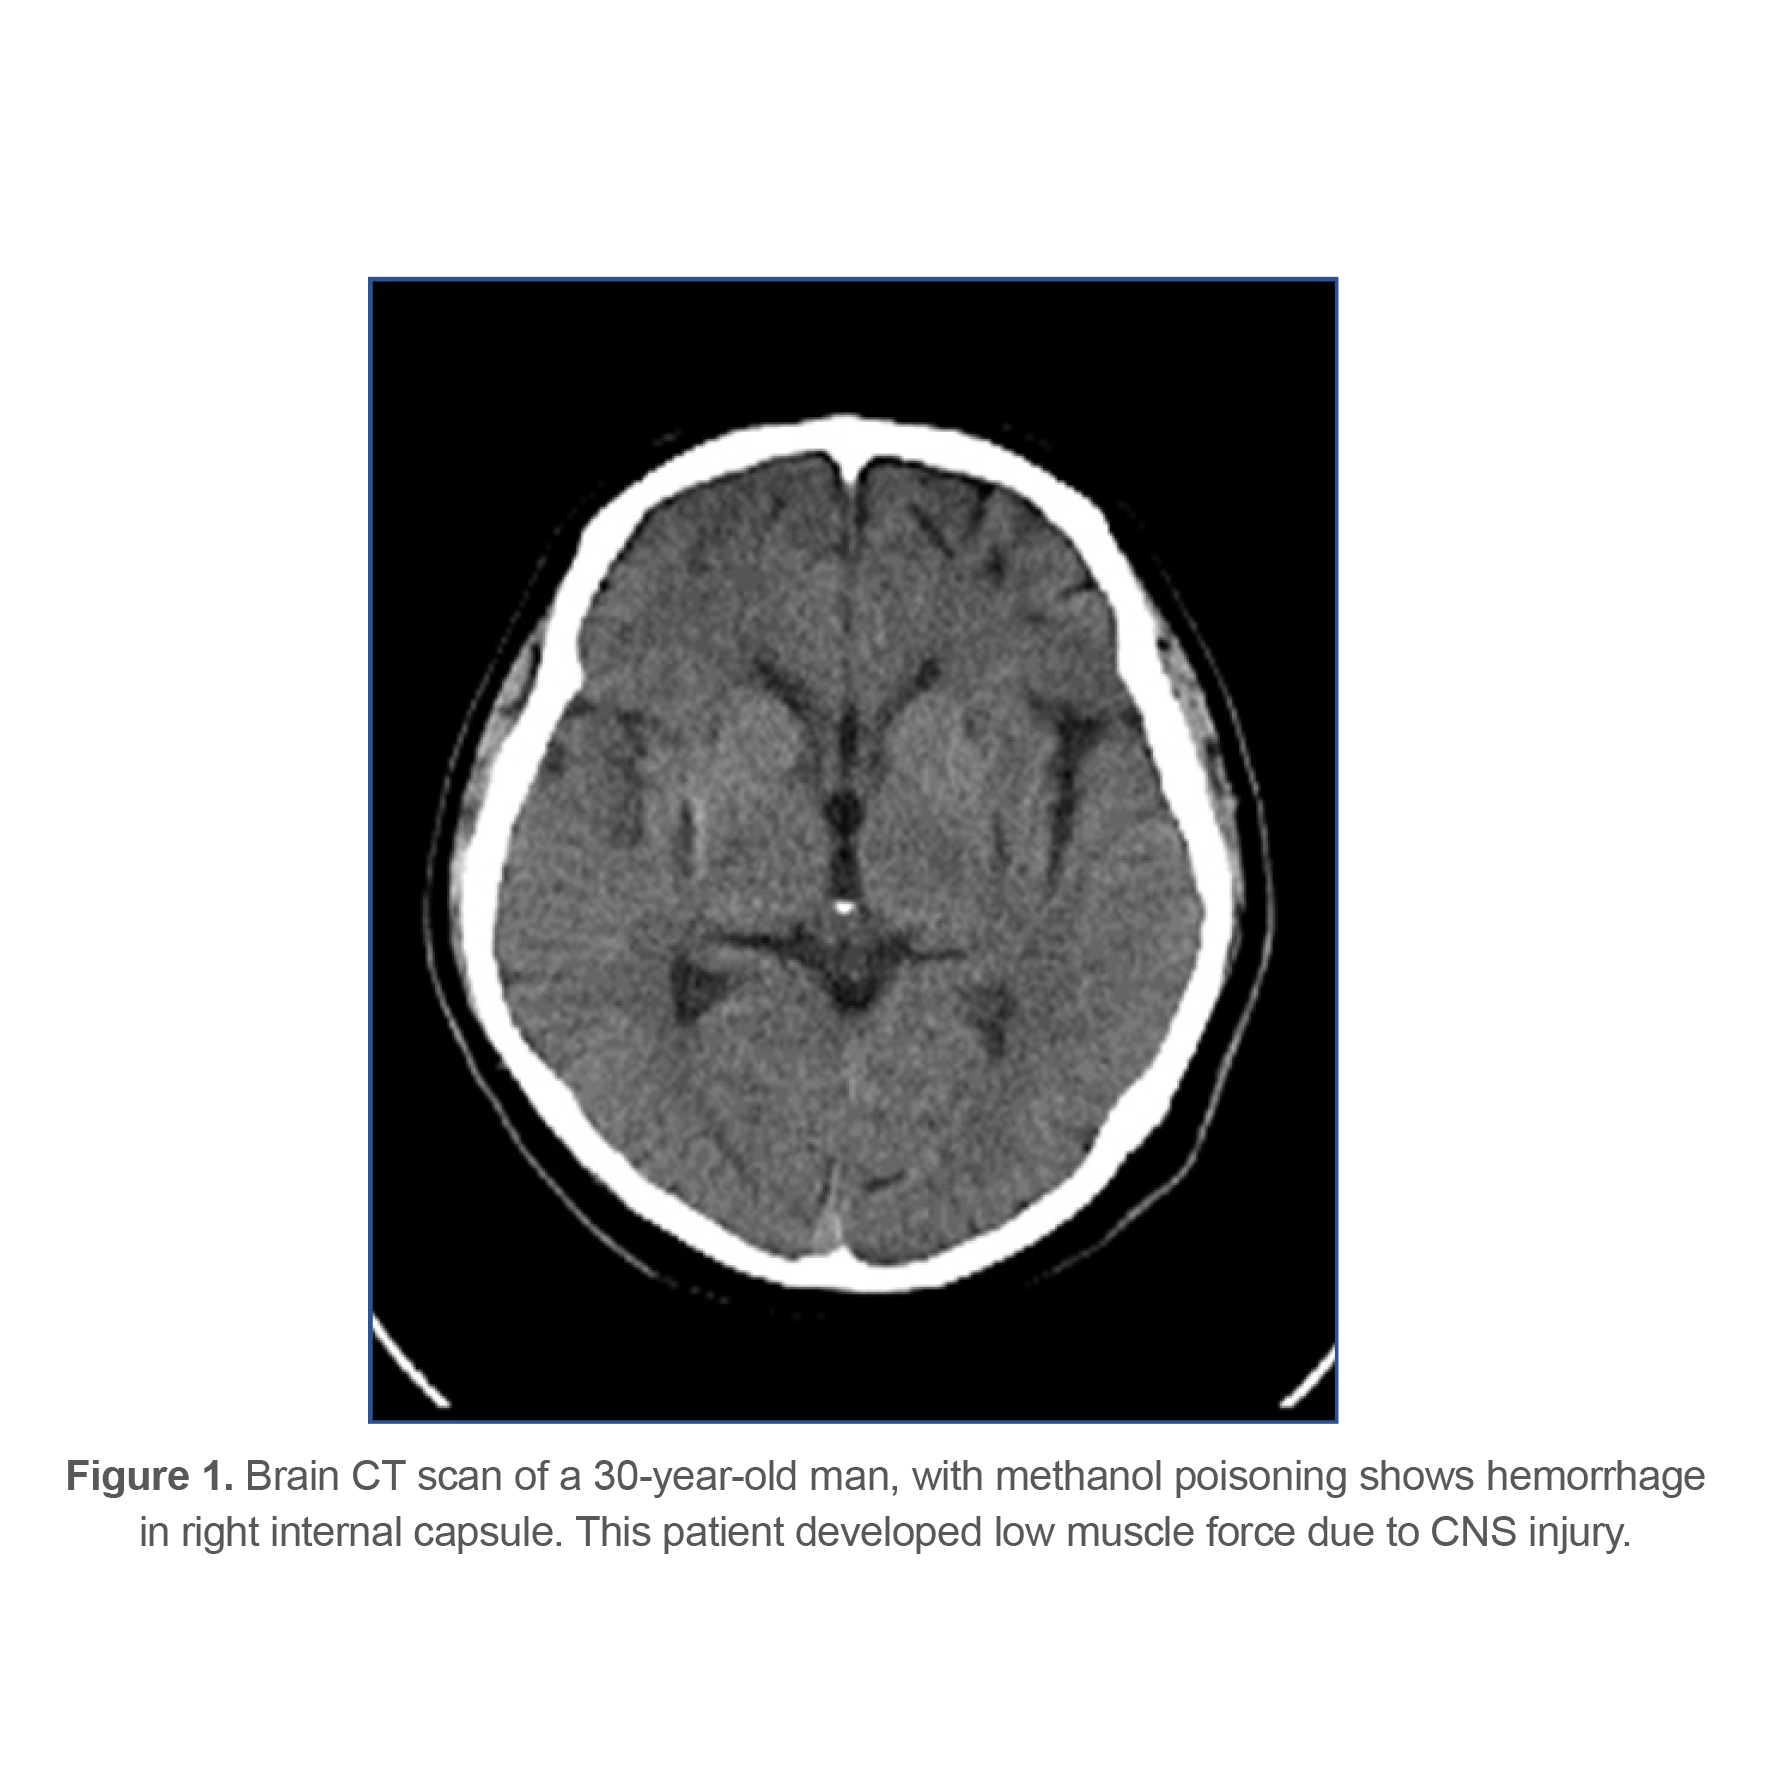

At last, 143 patients (77.72%) recovered completely, 27 patients (14.67%) had sequels at time of discharge from hospital and 14 patients (7.61%) died from methanol poisoning. Different types of complications and their frequency are listed in table 3. 21 patients (11.4%) had some sort of ophthalmologic complications at the time of discharge indicating that ophthalmologic complications were the most common complication among survivors. Figures 1-4 show brain CT scan of 4 patients with brain complications.

Brain CT scan of a 30-year-old man, with methanol poisoning shows hemorrhage in right internal capsule. This patient developed low muscle force due to CNS injury.